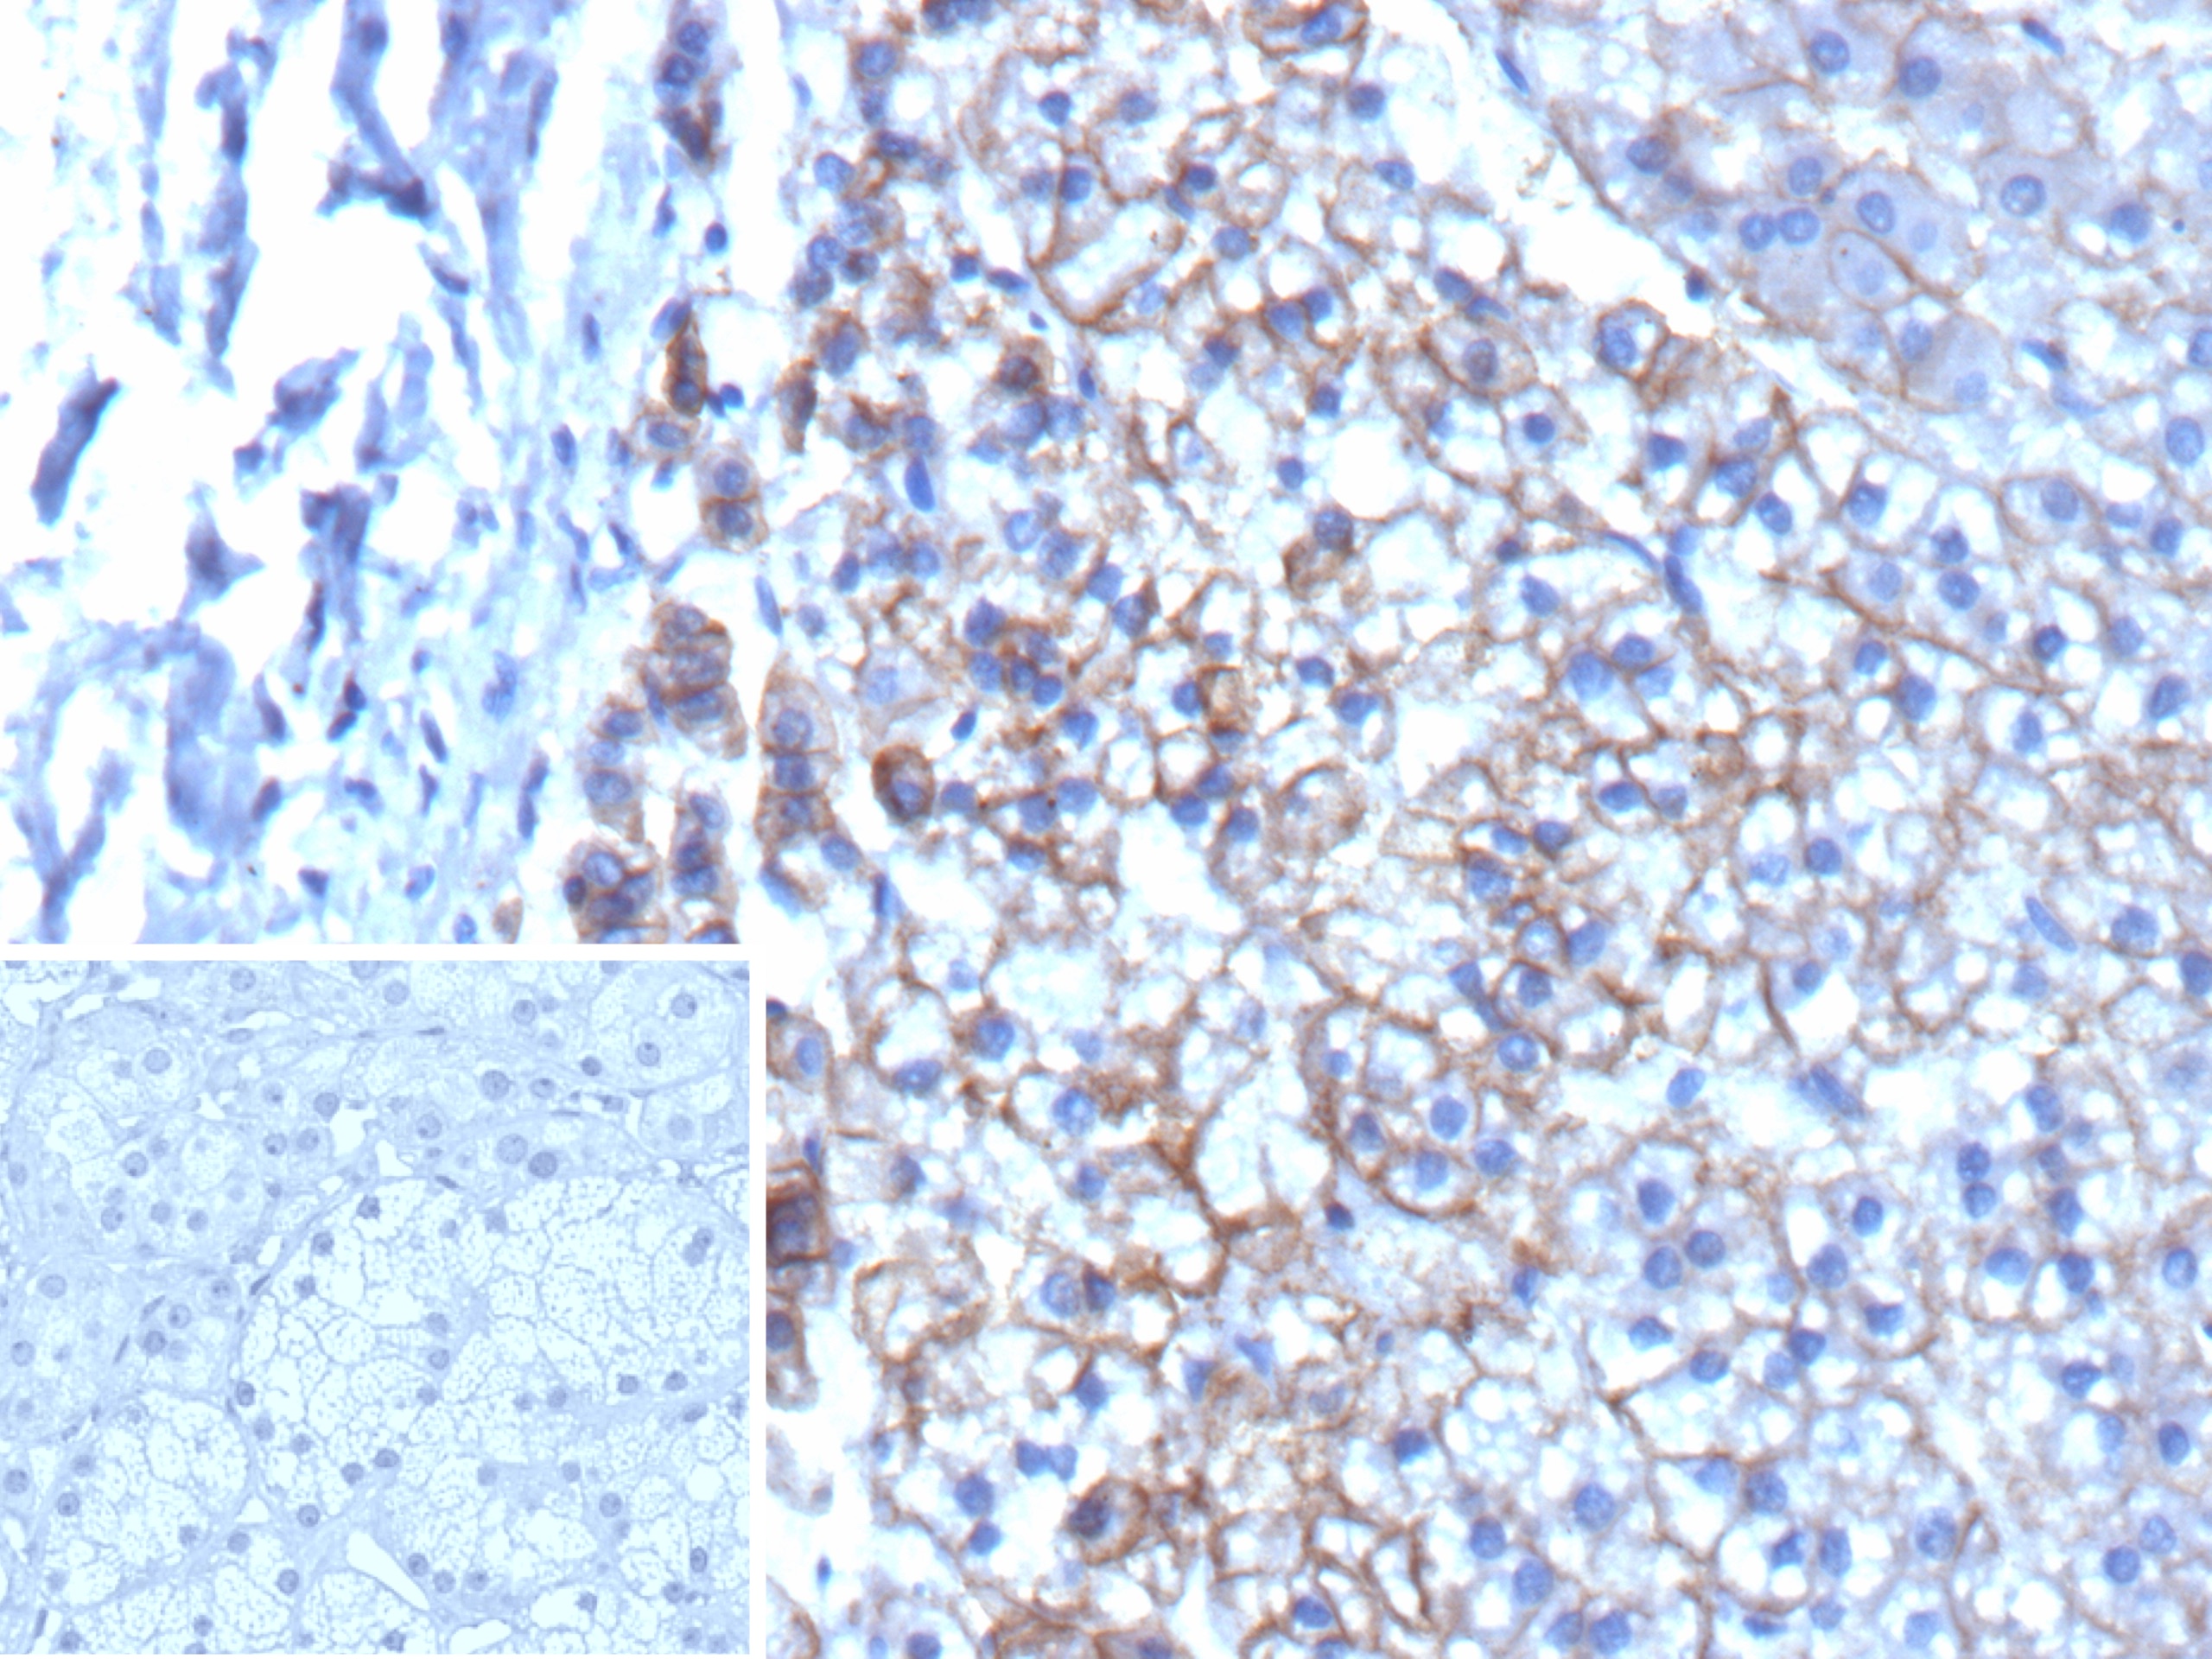

Formalin-fixed, paraffin-embedded human adrenal gland stained with MRP3 Recombinant Mouse Monoclonal Antibody (rDTX1). Inset: PBS instead of primary antibody; secondary only negative control.

The human multidrug resistance-associated protein (MRP) gene family contains at least 6 members designated MRP-1 to 6. MRP3 is a 190 to 200 kD integral membrane protein which is an organic anion transporter effective in transporting chemotherapeutic drugs such as MTX, etoposide and teniposide. Northern blotting of various human tissues has indicated MRP3 to be expressed in liver, colon, pancreas and at lower levels in the kidney. In liver, MRP3 is localized to the basolateral membrane of hepatocytes and is not associated with the canalicular membrane. MRP3 is also thought to play a role in bile production and secretion in the liver.